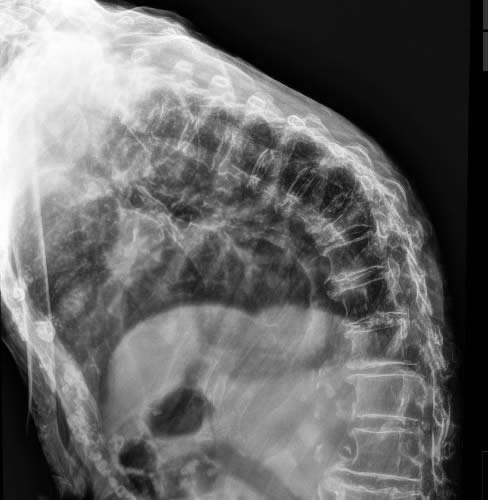

Οι ακτινογραφίες πραγματοποιούνται με πλήρως ψηφιακό εξοπλισμό και όχι ψηφιοποιημενο από έμπειρους Τεχνολόγους – Ακτινολόγους με άδεια ασκήσεως Επαγγέλματος.

Ο πιο σύγχρονος φορητός Ακτινολογικός εξοπλισμός πλήρως ψηφιακής απεικόνισης (DR) σε μια κινητή ακτινολογική μονάδα, μπορεί να επισκεφθεί τον ασθενή οπουδήποτε στην περιοχή της Θεσσαλονίκης και των περιχώρων και να σταλεί, αν ο ασθενής το επιθυμεί, η γνωματευμένη ακτινογραφία ηλεκτρονικά μέσω διαδικτύου στον θεράποντα- παραπέμποντα ιατρό ο οποίος θα λάβει το αποτέλεσμα στο προσωπικό του υπολογιστή, tablet, Smartphone οπουδήποτε κι αν βρίσκεται.